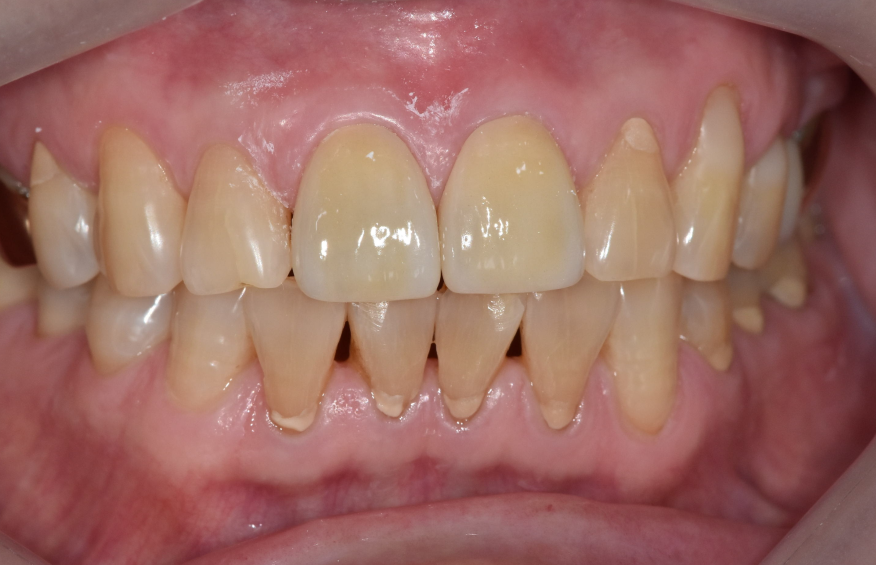

최종적으로 앞니 2개를 지르코니아 크라운으로 완성했습니다.

옆 치아와 색도 자연스럽게 맞췄어요.

250721

240605 (전) 250721 (후) 앞니 금 갔을 때, 방치하면 안 되는 진짜 이유 <파절 치료 사례>